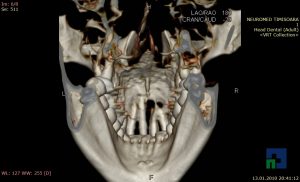

- Diagnosticul traumatismelor de bază de craniu

- Diagnosticul fracturilor:

- Complexe cranio-sinusale

- Complexe cranio-etmoidale

- Complexe cranio-orbitare

- Complexe cranio-faciale